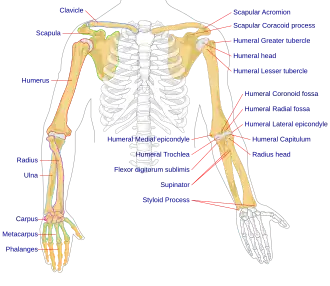

The humerus (/ˈhjuːmərəs/; pl.: humeri) is a long bone in the arm that runs from the shoulder to the elbow. It connects the scapula and the two bones of the lower arm, the radius and ulna, and consists of three sections. The humeral upper extremity consists of a rounded head, a narrow neck, and two short processes (tubercles, sometimes called tuberosities). The shaft is cylindrical in its upper portion, and more prismatic below. The lower extremity consists of 2 epicondyles, 2 processes (trochlea and capitulum), and 3 fossae (radial fossa, coronoid fossa, and olecranon fossa). As well as its true anatomical neck, the constriction below the greater and lesser tubercles of the humerus is referred to as its surgical neck due to its tendency to fracture, thus often becoming the focus of surgeons.

Articulations

At the shoulder, the head of the humerus articulates with the glenoid fossa of the scapula. More distally, at the elbow, the capitulum of the humerus articulates with the head of the radius, and the trochlea of the humerus articulates with the trochlear notch of the ulna.

Nerves

The axillary nerve is located at the proximal end, against the shoulder girdle. Dislocation of the humerus's glenohumeral joint has the potential to injure the axillary nerve or the axillary artery. Signs and symptoms of this dislocation include a loss of the normal shoulder contour and a palpable depression under the acromion.

The radial nerve follows the humerus closely. At the midshaft of the humerus, the radial nerve travels from the posterior to the anterior aspect of the bone in the spiral groove. A fracture of the humerus in this region can result in radial nerve injury.

The ulnar nerve lies at the distal end of the humerus near the elbow. When struck, it can cause a distinct tingling sensation, and sometimes a significant amount of pain. It is sometimes popularly referred to as 'the funny bone', possibly due to this sensation (a "funny" feeling), as well as the fact that the bone's name is a homophone of 'humorous'.[4] It lies posterior to the medial epicondyle, and is easily damaged in elbow injuries.

Muscular attachment

The deltoid originates on the lateral third of the clavicle, acromion and the crest of the spine of the scapula. It is inserted on the deltoid tuberosity of the humerus and has several actions including abduction, extension, and circumduction of the shoulder. The supraspinatus also originates on the spine of the scapula. It inserts on the greater tubercle of the humerus, and assists in abduction of the shoulder.

The pectoralis major, teres major, and latissimus dorsi insert at the intertubercular groove of the humerus. They work to adduct and medially, or internally, rotate the humerus.

The infraspinatus and teres minor insert on the greater tubercle, and work to laterally, or externally, rotate the humerus. In contrast, the subscapularis muscle inserts onto the lesser tubercle and works to medially, or internally, rotate the humerus.

The biceps brachii, brachialis, and brachioradialis (which attaches distally) act to flex the elbow. (The biceps do not attach to the humerus.) The triceps brachii and anconeus extend the elbow, and attach to the posterior side of the humerus.

The four muscles of supraspinatus, infraspinatus, teres minor and subscapularis form a musculo-ligamentous girdle called the rotator cuff. This cuff stabilizes the very mobile but inherently unstable glenohumeral joint. The other muscles are used as counterbalances for the actions of lifting/pulling and pressing/pushing.